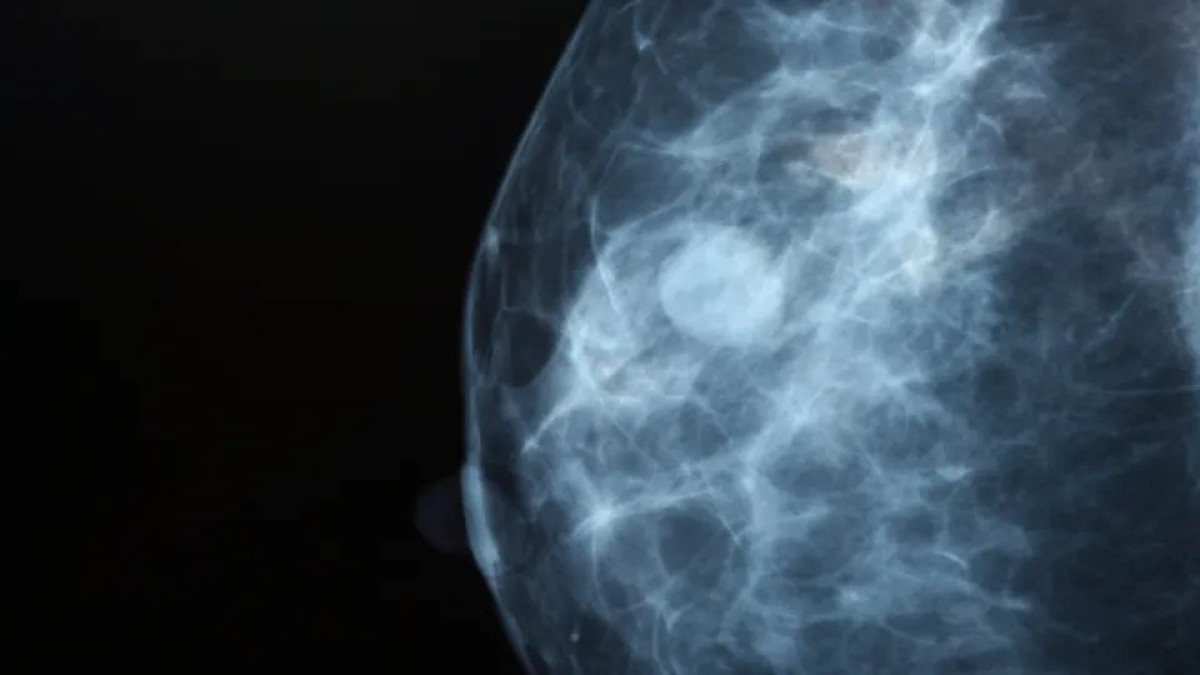

Καρκίνος Μαστού: Η AI εντοπίζει 20% περισσότερους όγκους, ταχύτερα με μεγαλύτερη ακρίβεια

Μια νέα, ελπιδοφόρα πραγματικότητα διαμορφώνεται στον τομέα της ιατρικής απεικόνισης, καθώς η μεγαλύτερη κλινική δοκιμή παγκοσμίως για τη χρήση της Τεχνητής Νοημοσύνης (AI) στον προσυμπτωματικό έλεγχο του καρκίνου του μαστού επιβεβαιώνει πως η τεχνολογία δεν αποτελεί απλώς ένα βοηθητικό εργαλείο, αλλά έναν κρίσιμο σύμμαχο. Η μελέτη MASAI, που διεξήχθη από το Πανεπιστήμιο της Lund στη Σουηδία, αποκαλύπτει ότι η μαστογραφία που υποστηρίζεται από AI μπορεί να εντοπίσει περισσότερους καρκίνους σε πρώιμο στάδιο, μειώνοντας παράλληλα δραστικά τον φόρτο εργασίας των ακτινολόγων.

Δημοσιευμένη στο έγκριτο ιατρικό περιοδικό The Lancet, η έρευνα ανέλυσε δεδομένα από περισσότερες από 100.000 γυναίκες στη Σουηδία. Πρόκειται για την πρώτη τυχαιοποιημένη ελεγχόμενη δοκιμή που εξετάζει την επίδραση της τεχνητής νοημοσύνης σε ένα εθνικό πρόγραμμα προσυμπτωματικού ελέγχου. Τα αποτελέσματα είναι εντυπωσιακά και προσφέρουν απτές αποδείξεις για την αποτελεσματικότητα των αλγορίθμων στην κλινική πράξη.

Τα ευρήματα έδειξαν ότι η υποβοηθούμενη από AI διαδικασία εντόπισε 20-29% περισσότερους καρκίνους συνολικά σε σύγκριση με την παραδοσιακή μέθοδο. Ακόμη πιο σημαντικό είναι το στοιχείο ότι η αύξηση αυτή δεν αφορούσε αμελητέα ευρήματα, αλλά κλινικά σημαντικούς καρκίνους. Συγκεκριμένα, εντοπίστηκαν 24% περισσότεροι διηθητικοί καρκίνοι και 51% περισσότεροι in situ καρκίνοι (προκαρκινικές αλλοιώσεις), επιτρέποντας την έγκαιρη παρέμβαση πριν η νόσο εξελιχθεί.